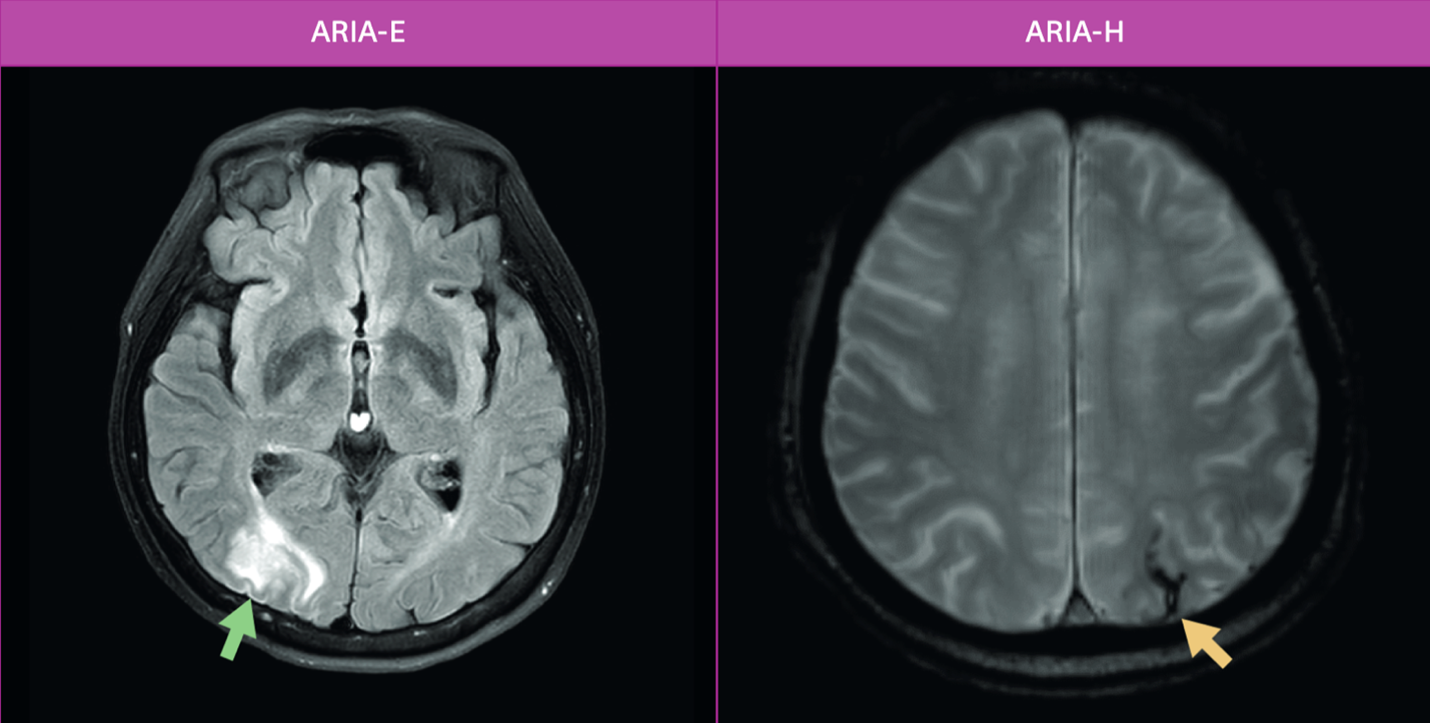

그러나 이러한 치료제들은 한계와 부작용 또한 명확하다. 가장 주된 부작용은 ARIA(Amyloid-Related Imaging Abnormalities)로, 뇌부종(ARIA-E)이나 미세출혈(ARIA-H) 형태로 나타난다. (그림 4. ARIA-E와 ARIA-H 사례)

이는 대부분 무증상이지만 드물게 심각한 신경학적 증상을 유발할 수 있어 정기적인 MRI 모니터링이 필수적이다. 대한치매학회의 최신 권고안에 따르면, 치료 전 뇌 MRI를 통해 출혈 위험이 높은 병변 여부를 확인하고, 항응고제 사용자나 최근 1년 이내 뇌경색 병력이 있는 환자에게는 투약을 피하는 등 치료 여부를 신중히 결정해야 한다. 또한 고가의 약제비와 주사제 투여를 위한 인프라 구축(주입 센터, MRI 판독 전문성 등)은 실제 임상 도입의 장벽으로 작용하고 있다. 미국 워싱턴 대학의 실제 임상 적용 사례(Real-world data)는 이러한 치료가 전문 클리닉 내 체계적인 프로토콜 하에 안전하게 수행될 수 있음을 보여주지만, 동시에 상당한 의료 자원이 소모됨을 시사한다.